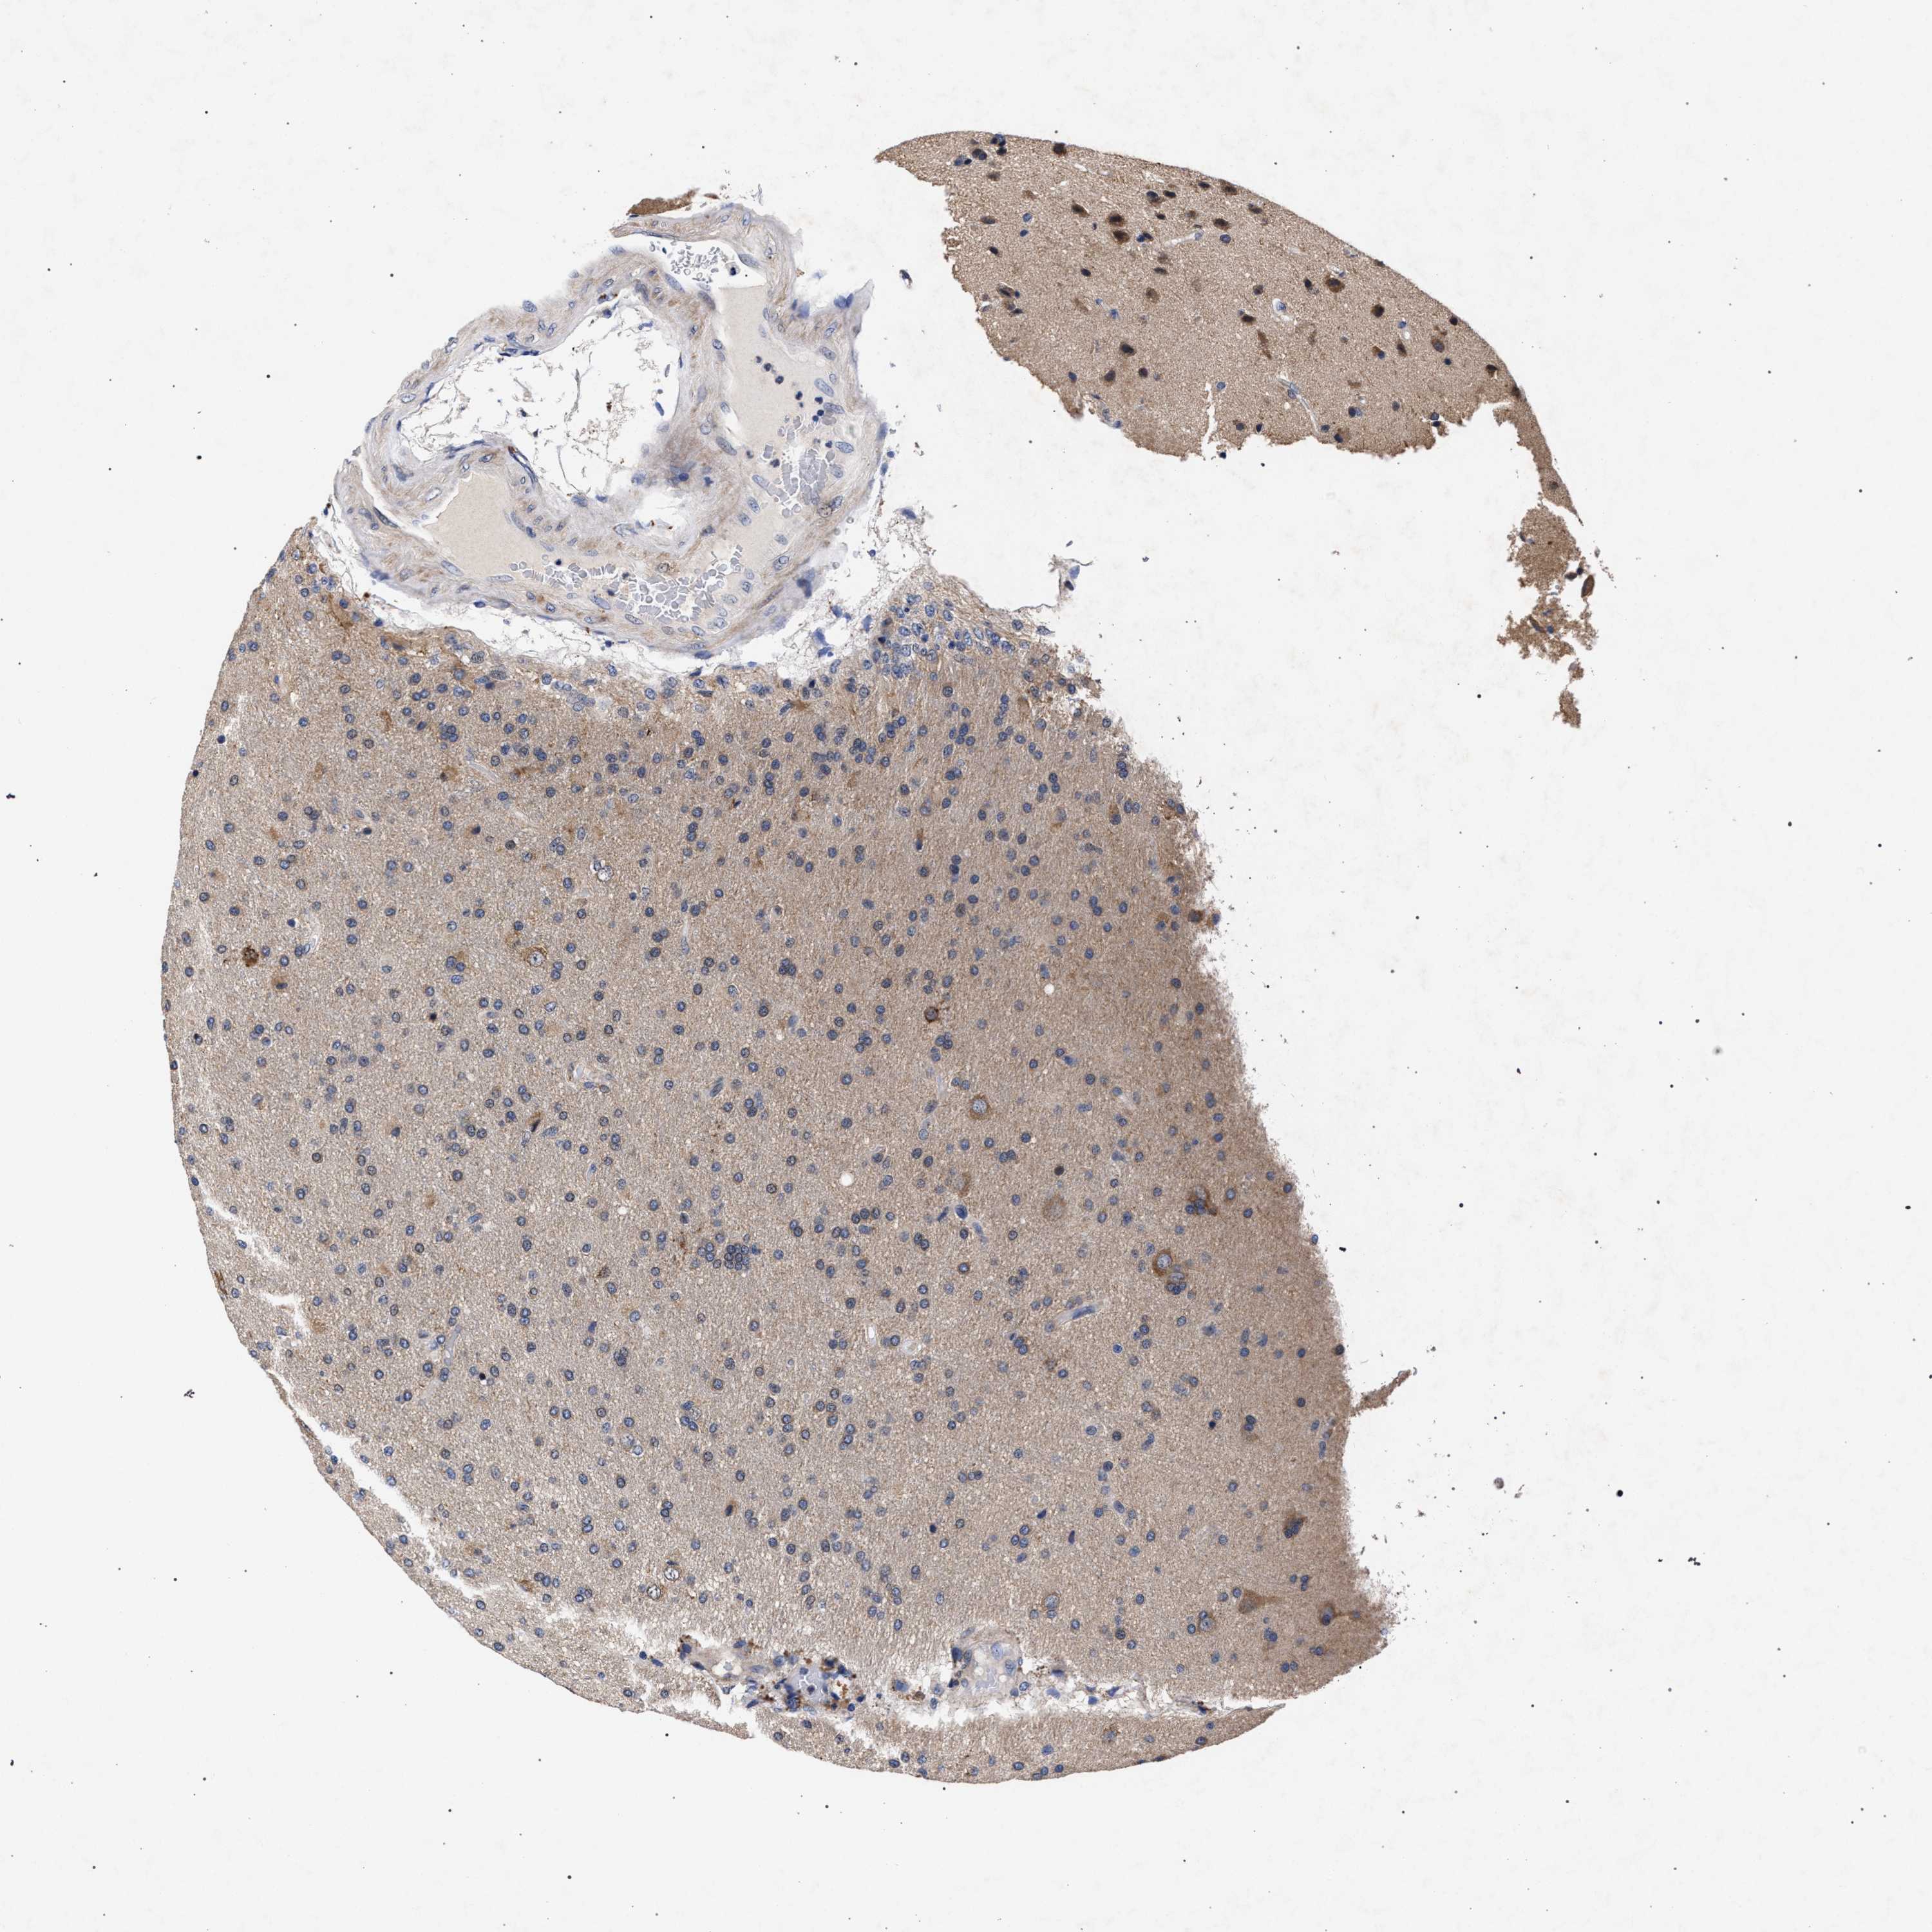

GLIOMA - Protein expressioni

A mouse-over function shows sample information and annotation data. Click on an image to view it in a full screen mode. Samples can be filtered based on level of antibody staining by selecting one or several of the following categories: high, medium, low and not detected. The assay and annotation is described here.

Antibody stainingi

Antibody staining in the annotated cell types in the current human tissue is reported as not detected, low, medium, or high, based on conventional immunohistochemistry profiling in selected tissues. This score is based on the combination of the staining intensity and fraction of stained cells.

Each image is clickable and will lead to virtual microscopy that enables deeper exploration of all samples and also displays staining intensity scores, fraction scores and subcellular localization as well as patient and tissue information for each sample.

Antibody HPA021261

Antibody HPA021325

Staining

High

Medium

Low

Not detected

Intensity

Strong

Moderate

Weak

Negative

Quantity

>75%

75%-25%

<25%

None

Location

Nuclear

Cytoplasmic/membranous

Cytoplasmic/membranous,nuclear

Glioma, malignant, High grade

Glioma, malignant, Low grade